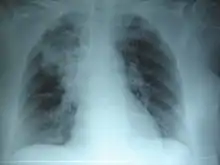

CFTR، نوعی کانال کلریدی تنظیم شونده با CAMP است که سایر کانالهای یونی را تنظیم میکند. CFTR، هیدراتاسیون ترشحات در داخل راههای هوایی و مجاری را از طریق دفع کلراید و مهار برداشت سدیم حفظ میکند. اختلال عملکرد CFTR میتواند بر بسیاری از اعضای مختلف تأثیر بگذارد، خصوصاً اعضایی که مایع مخاطی ترشح میکنند مانند راههای تنفسی فوقانی و تحتانی، لوزالمعده، دستگاه صفراوی، دستگاه تناسلی مذکر، روده و غدد عرق، ترشحات بیآب و چسبنده در ریههای بیماران مبتلا به CF، جلوی کلیرانس مخاطی-مژکی را میگیرد.

عملکرد پپتیدهای طبیعی ضد میکروبی را مهار میکند و راه هوایی را مسدود مینماید. ظرف ماههای اول عمر، این ترشحات و باکتریهای جای گرفته در آنها نوعی واکنش التهابی را آغاز میکنند. رهاسازی سیتوکینهای التهابی، آنزیمهای ضد باکتریایی میزبان و آنزیمهای باکتریایی به نایژکها صدمه میزند. چرخههای راجعه عفونت، التهاب و تخریب بافتی، مقدار بافت ریوی واجد عملکرد را کاهش میدهند و سرانجام موجب نارسایی تنفسی میشوند.

CF بهطور کلاسیک در اوایل کودکی تظاهر میکند، هر چند تقریباً ۴ درصد بیماران در بزرگسالی تشخیص داده میشوند. ۱۰ تا ۲۰ درصد بیماران در بدو تولد با ایلئوس مکونیوم تظاهر میکنند و سایرین با شکایات تنفسی مزمن یا نارسایی رشد، یا هر دو در سنین بالاتر مراجعه میکنند. پیشرفت بیماری ریوی، عامل اصلی تعیینکننده ابتلا و مرگ و میر است. اکثر بیماران به علت نارسایی تنفسی بین ۳۰ تا ۴۰ سالگی فوت میکنند. شایعترین علائم بیماری مربوط به درگیری دستگاه تنفسی است؛ این علائم شامل سرفه همراه با خلط، خس خس سینه و عفونت ریهها میباشد در مواردی سینوزیت و پولیپهای بینی نیز مشاهده میشود. سایر علایم بیماری عبارتند از: دل دردهای عودکننده، کاهش وزن، اختلال در گوارش غذا، انسداد روده، تهوع و استفراغ، اسهال چرب، نارسایی در رشد و درگیری کبد.